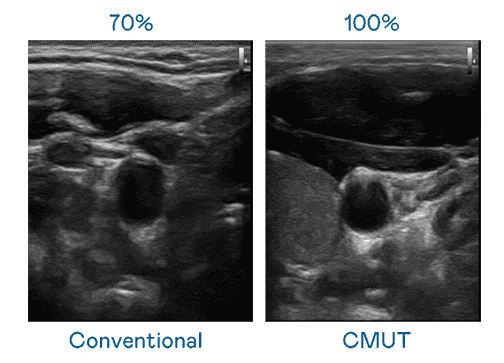

CMUT 技术是一种用电容式微机电元件来产生超音波讯号的技术。。。与传统 PZT 压电式技术相比,,CMUT 频宽增加 30%,,更宽频的超音波讯号让影像解析度大幅提升,,,是实现高影像品质医疗超音波扫描、、、促进精准医疗发展的关键技术。。。

大频宽带来超清晰影像

超音波影像的解析度高低,,,首先取决于探头能发出的讯号频宽。。。。z6尊龙 CMUT 可提供高清晰的超音波讯号,,提供高频宽、、高灵敏度、、、、影像纹理细节更高的超音波影像,,协助医护人员缩短影像判读时间及利用精准的医疗影像进行诊断。。。